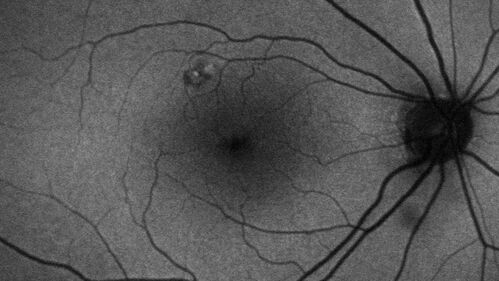

Pseudophakic CME chronic

74 year old man presented 14 weeks after cataract surgery with severe CME on topical therapy.  Multiple attempts to taper drops failed.  Also, the patient had a steroid responsive glaucoma.  He ended up on BID PF, Ketorolac and Dorz/Timolol